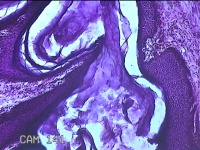

前胸部包块

性别

女

年龄

45岁

临床诊断

皮脂腺囊肿

一般病史

发现前胸部包块3个月余。

标本名称

大体所见

灰白暗红色组织2.2x1x0.8cm一块,表面带梭形皮肤2.2x1.3cm,皮下见包块1.8x1.2x0.8一块,切开包块呈实性,切面灰白粉红色,质软。